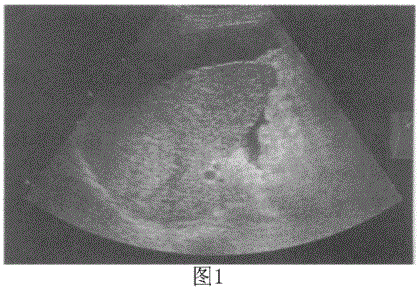

问题 临床资料:男,46岁,常规体检。 超声综合描述:图1二维超声扫查:肝表面不平,呈波浪状,肝回声明显不均,三支肝静脉变细,右叶可见3.9cm×4.0cm中强回声区,内回声不均,周边有晕;肝前、肝周可见无回声,深度1.9cm。下列彩图采用三维表面成像技术扫查:清楚显示肝表面波浪状不平及右叶增强回声区三雏空间立体结构。 {图1} 超声提示:

选项 A.肝硬化肝癌腹水 B.肝硬化肝血管瘤腹水 C.肝硬化肝局灶性增生腹水 D.肝硬化肝腺瘤腹水

答案 A